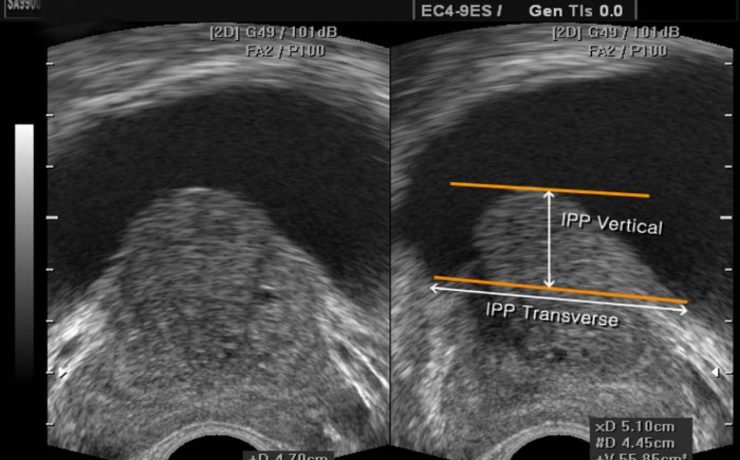

La ecografía del bazo.

La ecografía del bazo La ecografía del bazo es una parte fundamental del examen ecográfico completo, en el cual se evalúa el tamaño, forma, ubicación y parénquima del bazo, siendo necesario examinar y documentar estos aspectos detalladamente. Una de las principales ventajas de la ecografía es su amplia disponibilidad, bajo